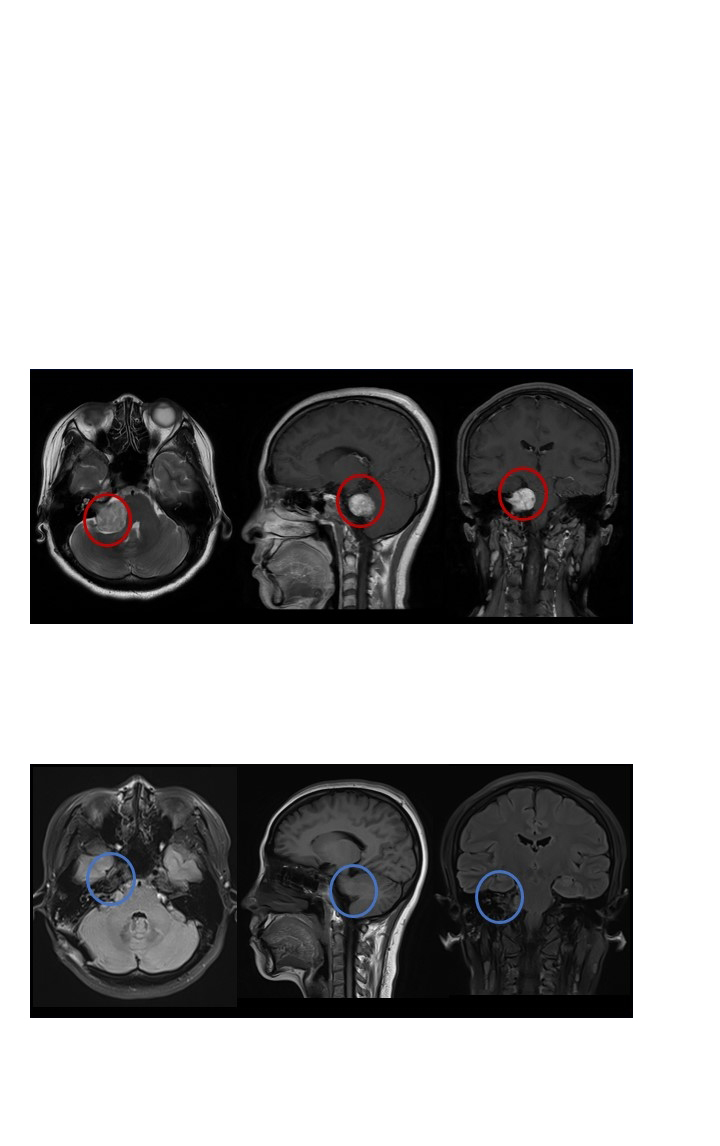

2021年12月,影像檢查顯示:右側(cè)CPA區(qū)可見團塊狀T2稍高信號,T1稍低信號,病灶大小約為25*26*25mm,累及右側(cè)內(nèi)聽道內(nèi),增強掃描顯示明顯強化,DWI未見明顯彌散受限,ADC、FLAIR未見明顯異常信號。橋腦及右側(cè)橋臂受壓,四腦室變形。

巴教授在對小瑞的病情詳細分析后回復(fù)表示,她患的是一種典型的(右側(cè))前庭神經(jīng)鞘瘤,較大直徑為35毫米(包括內(nèi)聽道內(nèi)的部分),腫瘤已經(jīng)壓迫腦干,有明顯的手術(shù)指征,建議手術(shù)治療。謹慎的評估切除率為99-全切,除非腫瘤與鄰近神經(jīng)(耳蝸神經(jīng)和面神經(jīng))之間有嚴重的粘連,在這種情況下,切除率可能是大概率。手術(shù)風險很低,在巴教授以往10余年的手術(shù)經(jīng)驗中,沒有出現(xiàn)過術(shù)中血管損傷或面神經(jīng)損傷,導(dǎo)致長期性面癱等情況。但由于小瑞術(shù)前已經(jīng)出現(xiàn)輕度面癱和聽力下降,這意味著面聽神經(jīng)受到相當嚴重的壓迫,手術(shù)解除腫瘤占位效應(yīng)后,術(shù)前癥狀在術(shù)后將逐漸好轉(zhuǎn)并較終恢復(fù)正常。